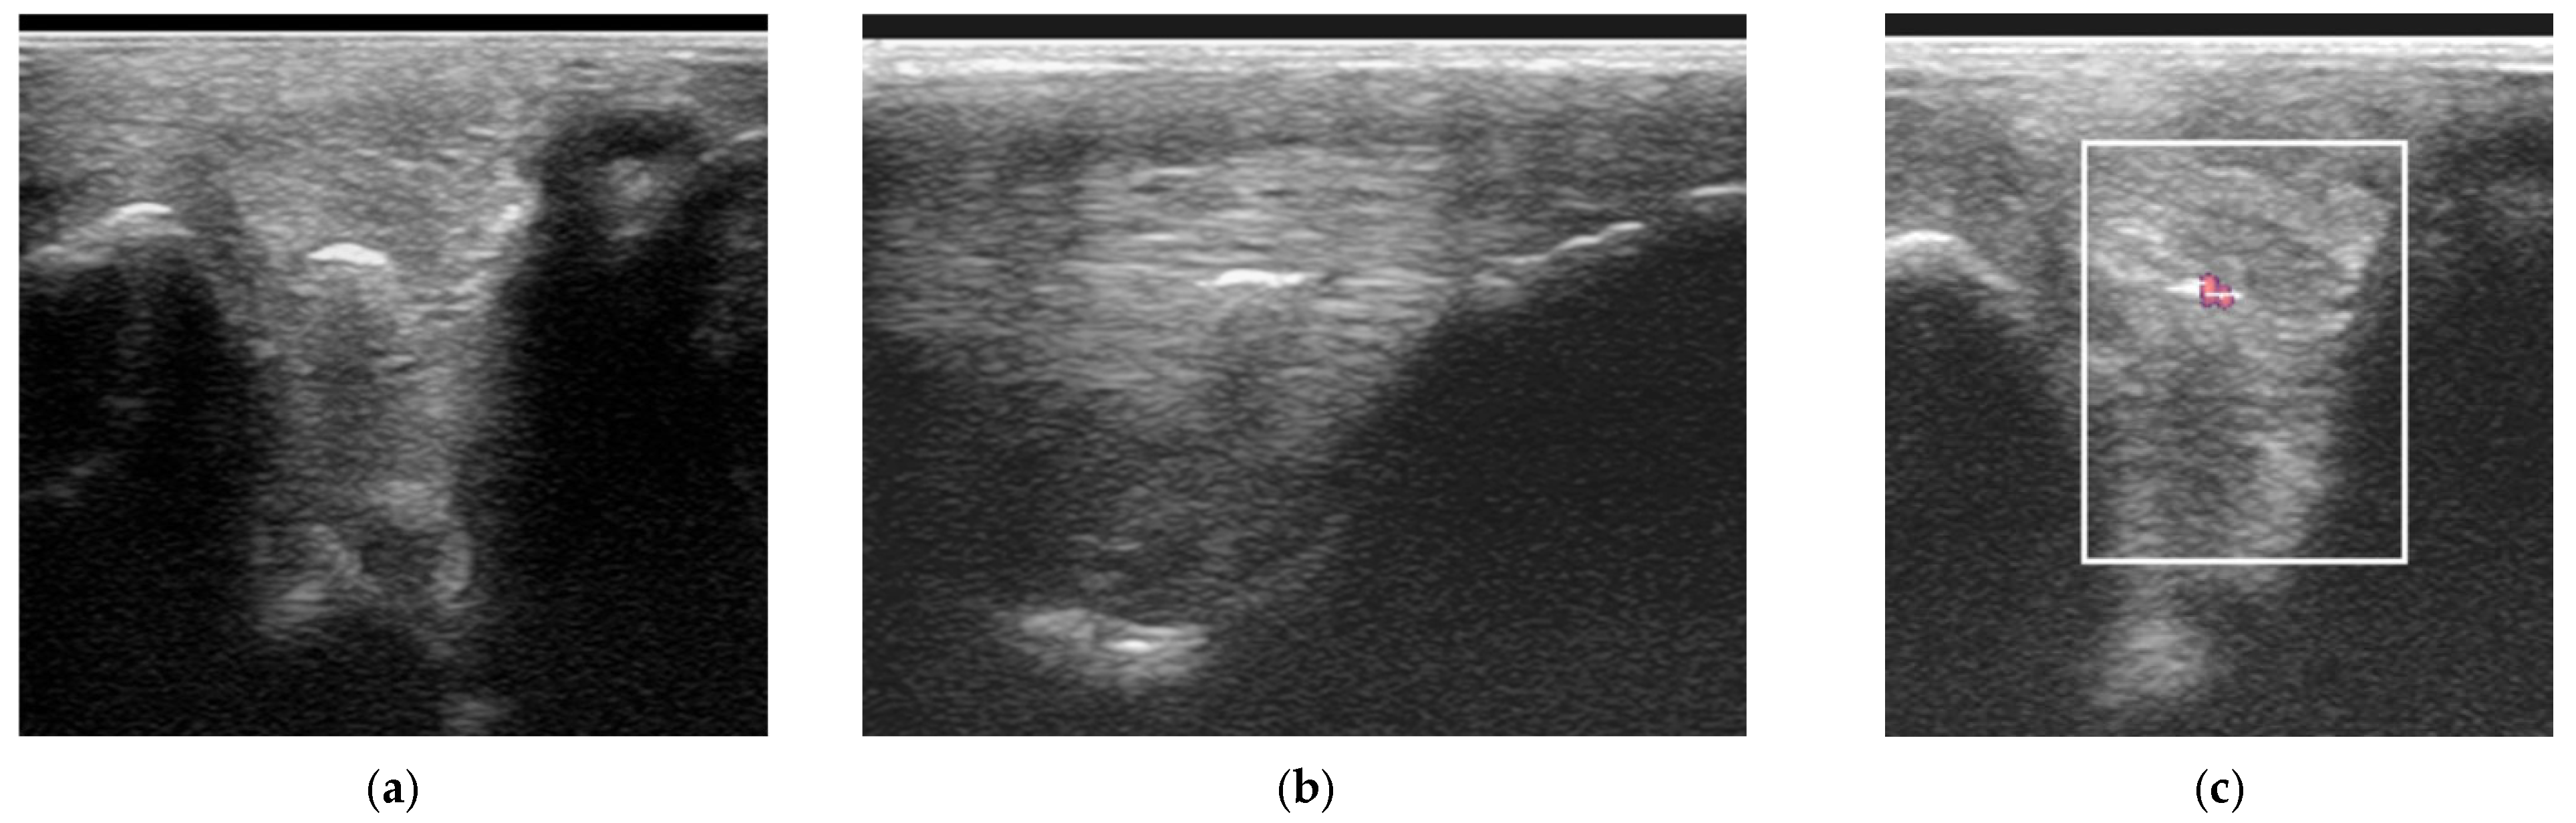

Figure 8. Longitudinal ultrasonographic images of the lateral branch of the suspensory ligament (SL) of a right forelimb of a four-year-old gelding (a,b) before treatment and (c) six months later; proximal is to the left. (a) There is loss of long linear parallel echoes in the dorsal aspect of the SL close to the enthesis. There is irregularity of the surface of the proximal sesamoid bone (PSB). (b) There was mild Doppler signal at the enthesis on the apex of the PSB. (c) At six months after treatment, a hypoechoic lesion persists, but there is no longer any power Doppler signal.